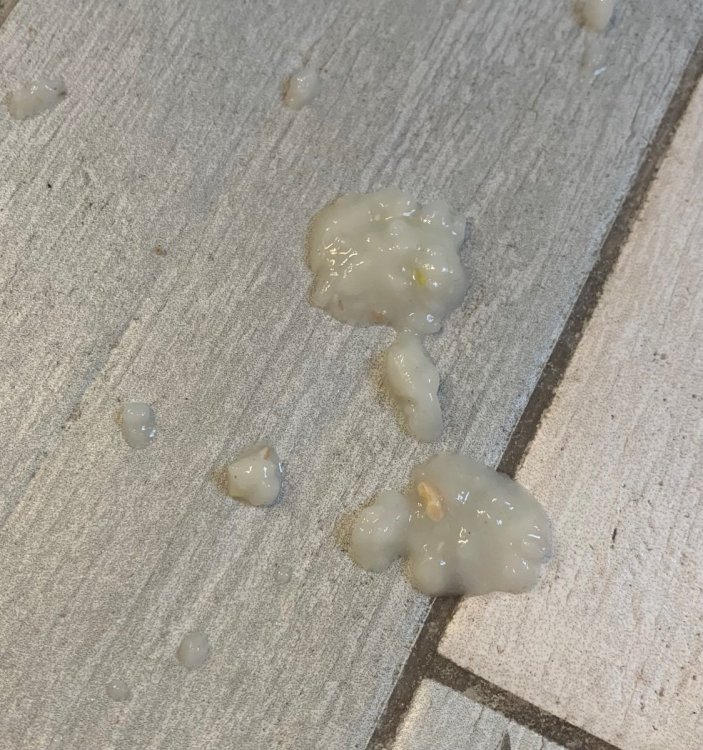

@маленький принц Сегодняшний вес 263гр. Все дозировки пересчитала на актуальный вес. Надеюсь, все верно. Лечение: -тилозин. Начат 9 сентября. Ориентируюсь давать минимум по 21 октября. Дозировка 70мг/кг. Набираю 0,6мл воды 0,1мл тилозина хорошо размешивают и выпаиваю 0,32мл полученного раствора 2 р/д. В одно время. -нистатин. Начат вместе с тилозином. Планировала давать еще неделю после окончания тилозина. Минимум по 28 октября. По 1/4 таблетки 2 раза в день. За 30-40 мин до еды. Натощак. Так как его нужно давать еще неделю и после амоксициллина, если я верно поняла, то ориентируюсь его давать до 8 ноября. -гепатовет по 0,1мл на 100гр дважды в день после еды. 0,26 сегодня буду давать. Начат так же сразу 9 сентября. Планирую давать на протяжении всего времени как даю противогрибковое. Да через 21 день остатки препарата выкидываю и покупаю новый. -Итраконазол. Дозировка 30 мг/кг/сутки. Сейчас у нас новая капсула в ней 495 пеллет. Значит с сегодняшнего дня даю по 20 пеллет два раза в день. Начат 6 октября. Не знаю какая продолжительность курса. -Юнидокс. 1/4 таблетки растворяю в 1мл воды и такого раствора выпаиваю по 0,41мл дважды в день. Храню в холодильнике сутки. Начат 6 октября. Курс 6 недель. Значит до 17 ноября. На время лечения убрать все источники кальция и витамина D. -Ацикловир. Начат в качестве профилактики, так как очень боялась заразить его оспой. 1/4 таблетки 400мг растворяю в воде и спаиваю этот раствор за два раза. Часть утром часть вечером. Начат 9 октября. Когда можно прекратить? -Амоксициллин Таблетки 250+62,5 мг Таблетку развожу в 5 мл воды спаиваю по 0,66мл дважды в день. Раствор храню в шприце с закрытым колпачком в холодильнике 5 суток. Перед отбором дозы взбалтываю. Начат 11 октября. Ориентировочная продолжительность приема 3 недели (до 1 ноября). Сама прекращать ничего не буду, все уточню. -Глюкоза. Одна часть физраствора две части глюкозы. Колю подкожно теплым. 3мл в сутки. Начата 2 октября. Не колола больше так как кормить стараюсь нормально, и его не сильно много рвало в последние дни. Но учитывая, как он стремительно тощает, может увеличить дозу? -Ципровет. По 0,1мл дважды в день подкожно в одно и то же время. Начат 15 октября вечером. Продолжительность не знаю. -Флуконазол. По 1,3мл дважды в день подкожно. Начат 15 октября вечером. Продолжительность не знаю. -отвар крапивы с 19 сентября 5 дней по 1мл 3 раза в день. Снова начат 6 октября. По 1мл 3 раза в сутки. Продолжаю давать. Или стоит прекратить? -Фоспренил. Давала два дня по 0,3мл. Наверное Фоспренил стоит подавать? По 0,26 раз в сутки. Верно? И на всякий случай, чтоб просто все в одном месте было для наглядности. Это то, что у нас было в лечении, но закончено: -глюконат кальция давала две недели с 18 сентября по 2 октября. По 0,1мл на 100гр 1 раз в сутки. -викасол с 5 октября по 0,1мл в сутки проколола 5 дней. Я вообще в ужасе, что с ним творится. Как стремительно он худеет. (Как когда-то набирал…). За 3 дня похудел на 30гр. Киль снова торчит. Его постоянно рвет. Я кормила его два дня киселем из пшеничной муки и воды, и было получше, он перестал постоянно рваться как с каши. Начала понемногу в этот кисель подмешивать каши, чтоб попитательнее было. Вот так это выглядит: Вечером покормила его этим киселем с кашей. Через час приблизительно его вырвало. Больше мучить не стала. Рано утром его снова начало рвать. И рвет его каким-то ужасом! Похоже на комок каши ярко зеленого цвета (фото не передает) со слизью! Рвет его просто бесконечно! Я с утра даже нистатин натощак задать не могла. У него рвотные позывы спазмы просто через каждые 5 минут. Наклоняется, трясется, рваться нечем, но его всего трясет колошматит… кошмар! Когда не рвет, сидит раздувает подклювье горло, прям надувает-сдувает быстро, как меха ходят, почти вибрация такая только с гораздо большей амплитудой и характерным звуком. Надеюсь, понятно, объяснила. Чуть успокоился, задала ему нистатин. Пытался вырвать, не получилось. Через полчаса покормила. Только его киселем-клейстером. Без каши. Через 20 минут снова вырвало. Последние два дня помет выглядит так: Сегодня с утра вот что выдал: Вообще с киселя у него преимущественно вода, никаких там сформированных крендельков.